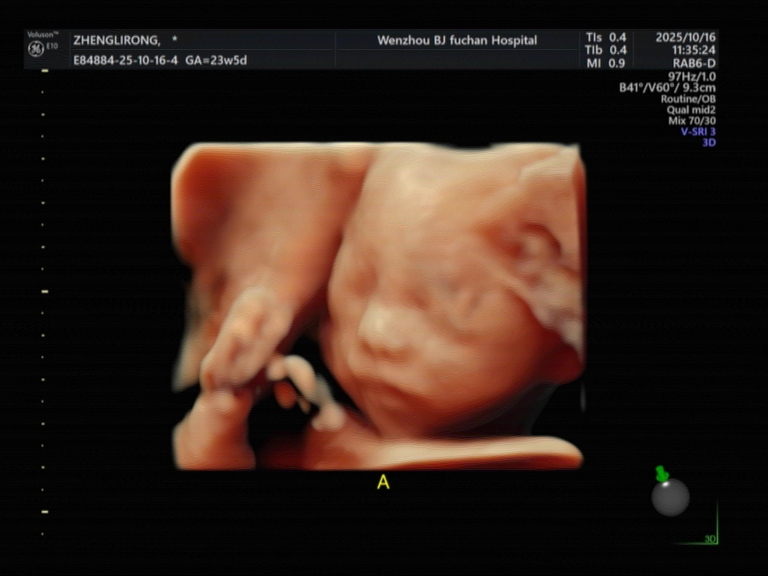

医院用的美国GE Voluson E10设备,宝宝五官看得超清晰